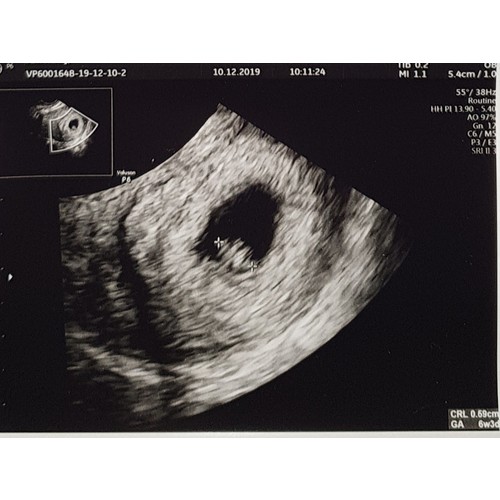

Mijn echo met 6 weken en 3 dagen. Kloppend hartje gezien.

Was wel met medische reden dat ik zo vroeg een echo heb gehad.

Nu de 27e weer een met 8 weken en 6 dagen.